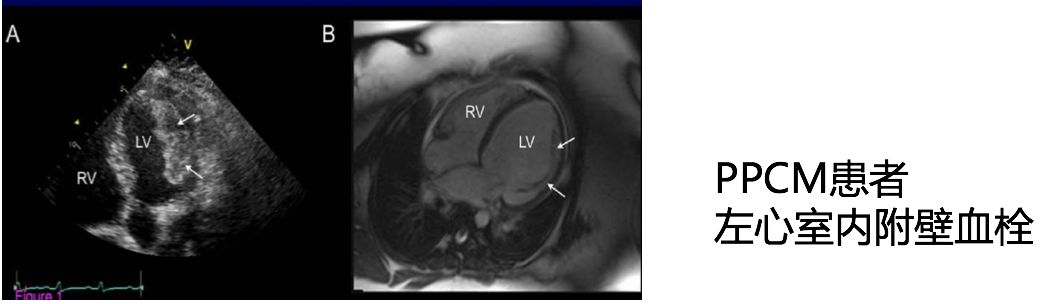

PPCM注册研究——30天的血栓栓塞事件

➤ 抗凝治疗